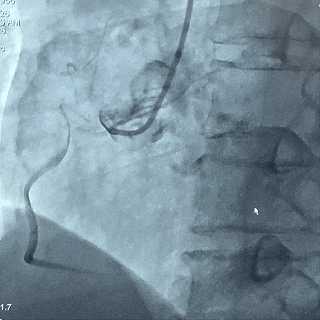

右冠造影

左冠造影

主动脉根部造影,瓣叶活动度差

20mm球囊扩张,轻微腰征无漏